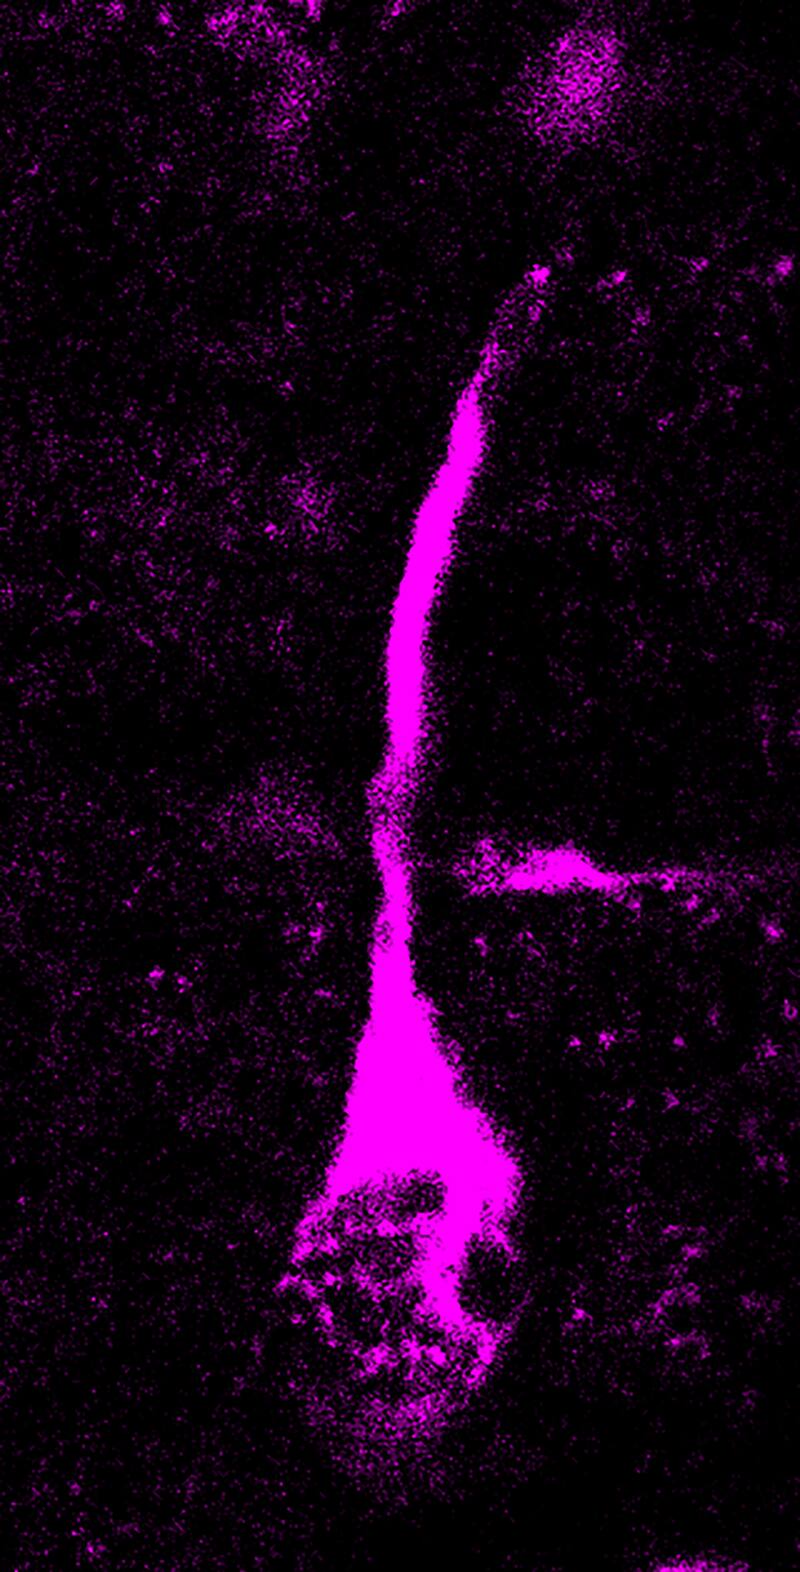

La TKTL1 humana moderna, pero no la TKTL1 neandertal, conduce a más neuronas en el neocórtex embrionario del ratón. Anneline y sus colegas introdujeron la variante humana moderna o neandertal de TKTL1 en la neocorteza de embriones de ratón. Observaron que las células gliales radiales basales, el tipo de progenitores neocorticales que se cree que son la fuerza impulsora para un cerebro más grande, aumentaron con la variante humana moderna de TKTL1 pero no con la variante neandertal. Como consecuencia, los cerebros de los embriones de ratón con el TKTL1 humano moderno contenían más neuronas.

Después de esto, los investigadores exploraron la relevancia de estos efectos para el desarrollo del cerebro humano. Con este fin, reemplazaron la arginina en el TKTL1 humano moderno con la lisina característica del TKTL1 neandertal, utilizando organoides de cerebro humano, estructuras en miniatura similares a órganos que se pueden cultivar a partir de células madre humanas en placas de cultivo celular en el laboratorio y que imitan aspectos de desarrollo temprano del cerebro humano.

“Descubrimos que con el tipo de aminoácido neandertal en TKTL1, se producían menos células gliales radiales basales que con el tipo humano moderno y, como consecuencia, también menos neuronas”, dijo Anneline Pinson en un comunicado. “Esto nos muestra que aunque no sabemos cuántas neuronas tenía el cerebro neandertal, podemos suponer que los humanos modernos tienen más neuronas en el lóbulo frontal del cerebro, donde la actividad TKTL1 es más alta, que los neandertales”.